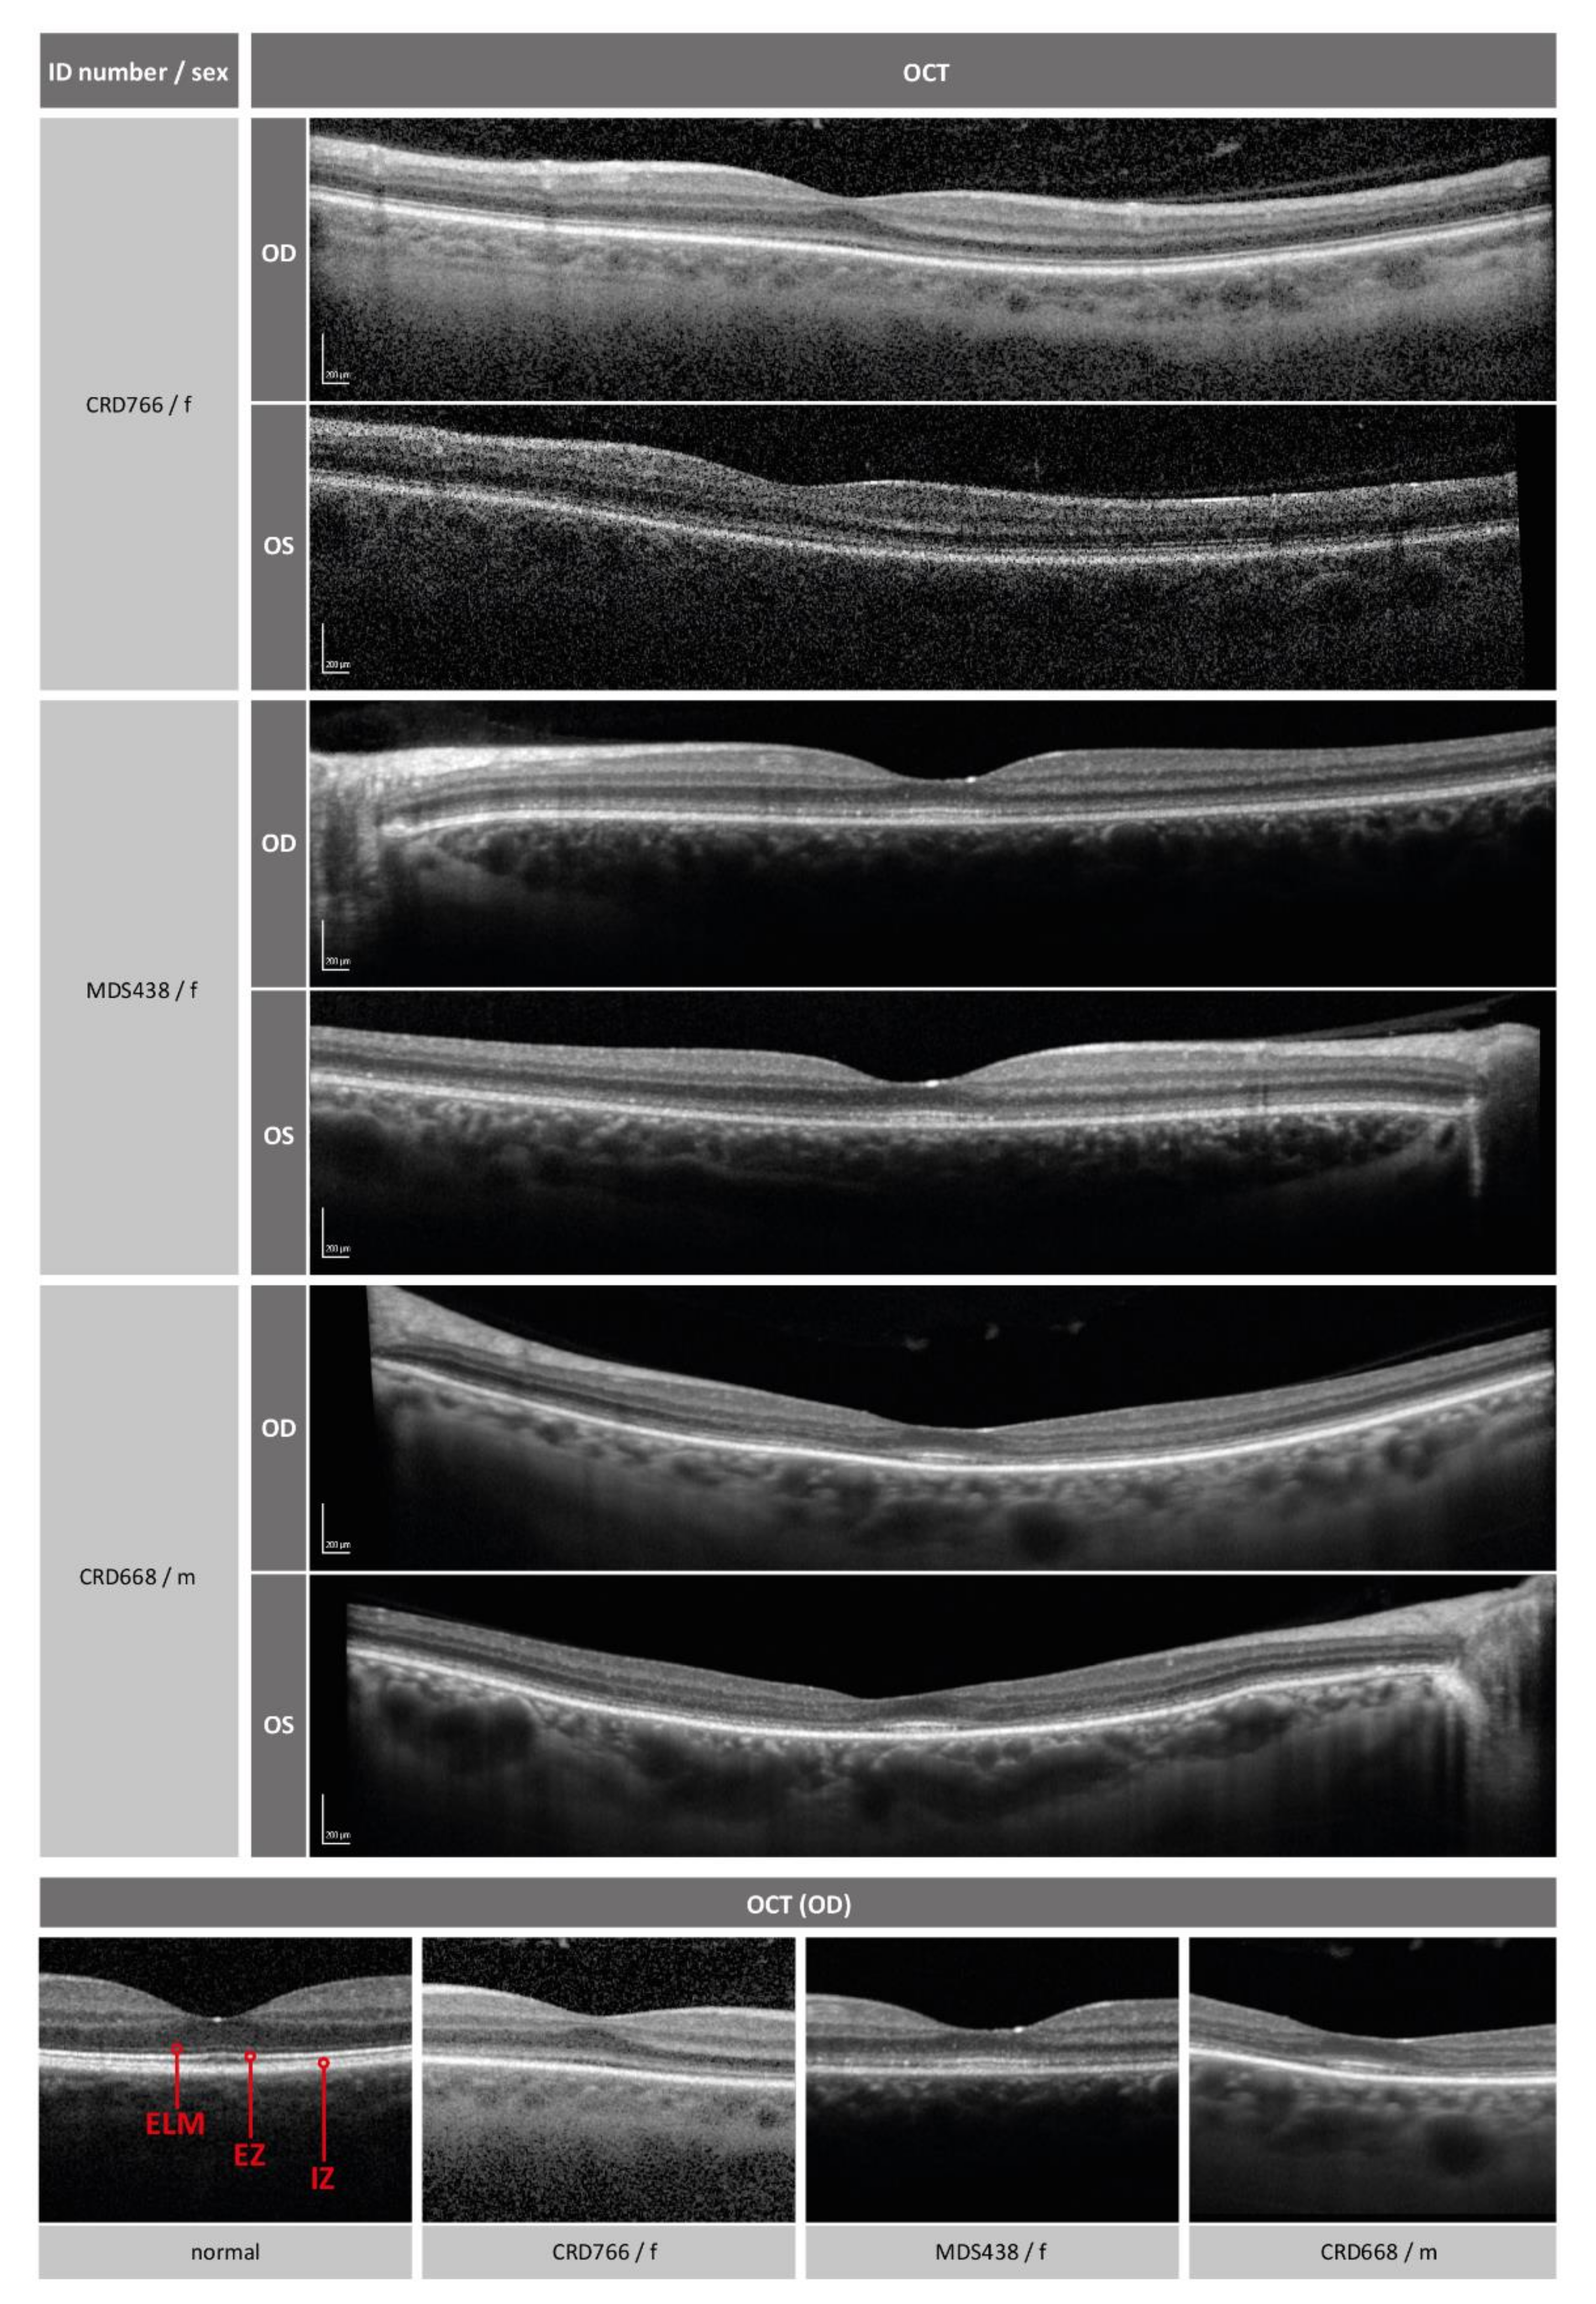

2.1. Clinical Phenotype